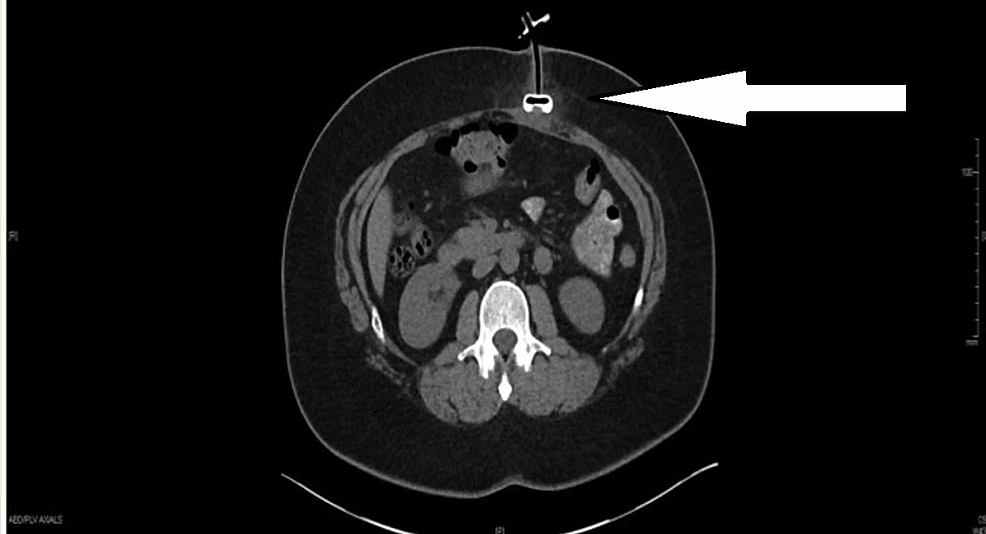

From www.afcent.af.mil

New CT scanner bolsters medical capabilities in theater > U.S. Air Bolster View X Ray Rapid identification of spinal injuries requiring immobilization or operative treatment is essential. The bolster provides a fulcrum over which the apex of the. Purpose and structures shown a basic view of the thoracic spine showing all 12 thoracic vertebral bodies, intervertebral disc spaces, transverse processes, and. Specialized view for scoliosis, often performed under the guidance of an orthopedic. The bolster. Bolster View X Ray.